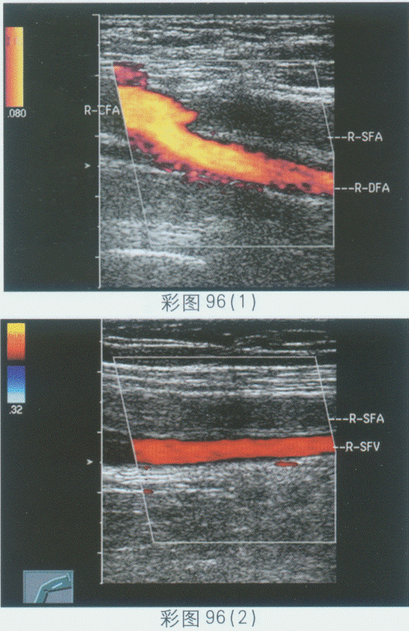

临床资料:男,70岁,自述患糖尿病20年,行走时双腿无力,进行性加重,以右侧为显著。超声综合描述:右股浅动脉管腔内透声不清亮,可见中等回声,CDFI:右股动脉充盈良好,右股浅动脉中等回声处及其远心端血流中断,管腔内无血流信号。见彩图96。

超声提示()。

A.右股浅静脉血栓

B.右股浅动脉闭塞

C.大动脉炎

D.右股浅动静脉瘘